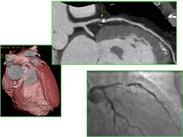

• 變異型心絞痛

628健康網為您分享有關變異型心絞痛的癥狀,變異型心絞痛的治療方法,變異型心絞痛的預防知識,變異型心絞痛的癥狀圖片,變...